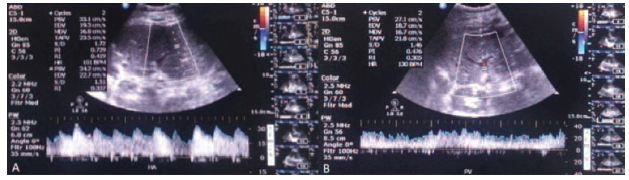

The surgical procedure was performed without complications, and the pathology revealed chronic hepatitis with microvesicular steatosis and biliary stasis. Within the first 3 days after LDLT, hemo-dynamic stability and progressive improvement of clinical data, including platelet count, coagulation profile, liver function, and bilirubin levels, were noted. In addition, daily follow-up Doppler sonography performed by an experienced radiologist on the transplant team showed patency of anastomotic and intrahepatic vessels without thrombosis. On the day after LDLT, she regained consciousness and began to receive tacrolimus. We monitored the plasma con-centration of tacrolimus, with levels of therapeutic drug monitoring of tacrolimus slowly increasing day by day (from 13.6 to 16.5 ng/mL). However, levels were still within the normal therapeutic range.

Four days after transplant, the patient had a seizure attack with loss of consciousness. Repeated brain magnetic resonance imaging scans showed diffuse swelling of cerebrum and cerebellum with uncal herniation and brainstem compression, so PRES progression was highly suspected. With thorough surveys of triggers, besides liver transplant, tacrolimus intoxication (therapeutic drug level of 21.4 ng/mL) was thought to be the primary cause to worsen PRES. Because of this, tacrolimus was promptly suspended. After the abrupt episode, rapid impairment of liver function, hyperbilirubinemia, thrombocytopenia, and prolonged prothrombin time/activated partial thromboplastin time occurred. Doppler sonography showed reduced flow of grafted intrahepatic vessels without thrombotic formation of anastomotic sites (Figure 2). An emergent computed tomography with contrast of abdomen showed hypo- and nonen-hancement (Figure 3), and gross hepatic infarction was diagnosed. The patient gradually deteriorated with sequential multiple organ failure and died 7 days after LDLT.